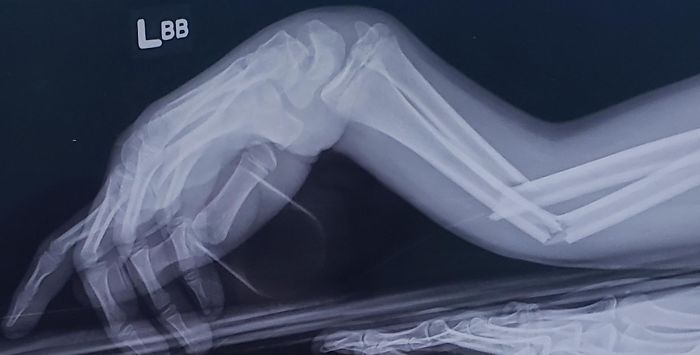

My (Nearly 60-Years-Old) Father's Arm After Being Thwomped By A Cow This Morning

Just A Bunch Of Grapes. Green Ones To Be Slightly More Specific